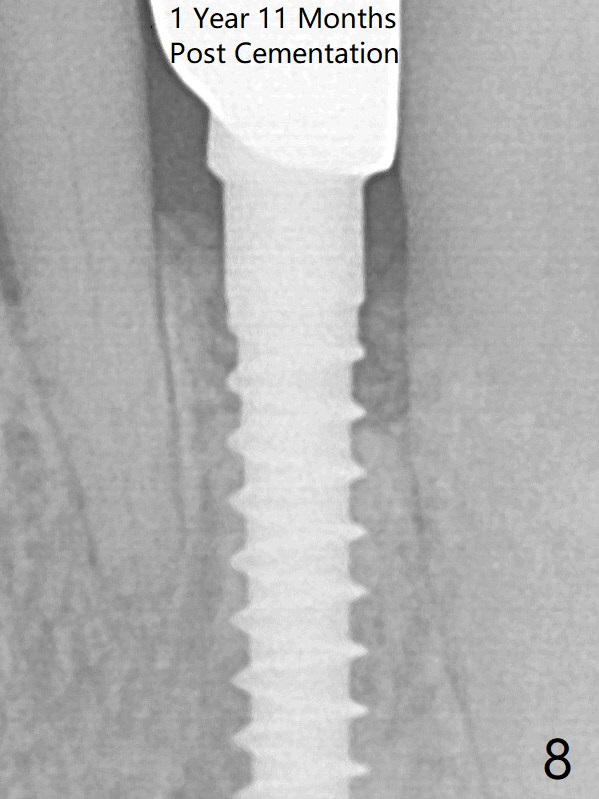

The gingival depth is measured 2-4 mm after extraction. The 1st intraop PA taken with 1.2 mm drill for 16 mm shows the mesiodistal width is 5.11 mm (Fig.2); a 2.5x14(2) mm 1-piece implant is placed with >35 Ncm (Fig.3 with allograft placed). There is no bone loss 3 months postop (Fig.5). The distal crest seems to be reduced in density and lower in height 1 year 7 months (Fig.7) and 1 year 11 months (Fig.8) post cementation. The severity does not worsen probably related to use of water pik.